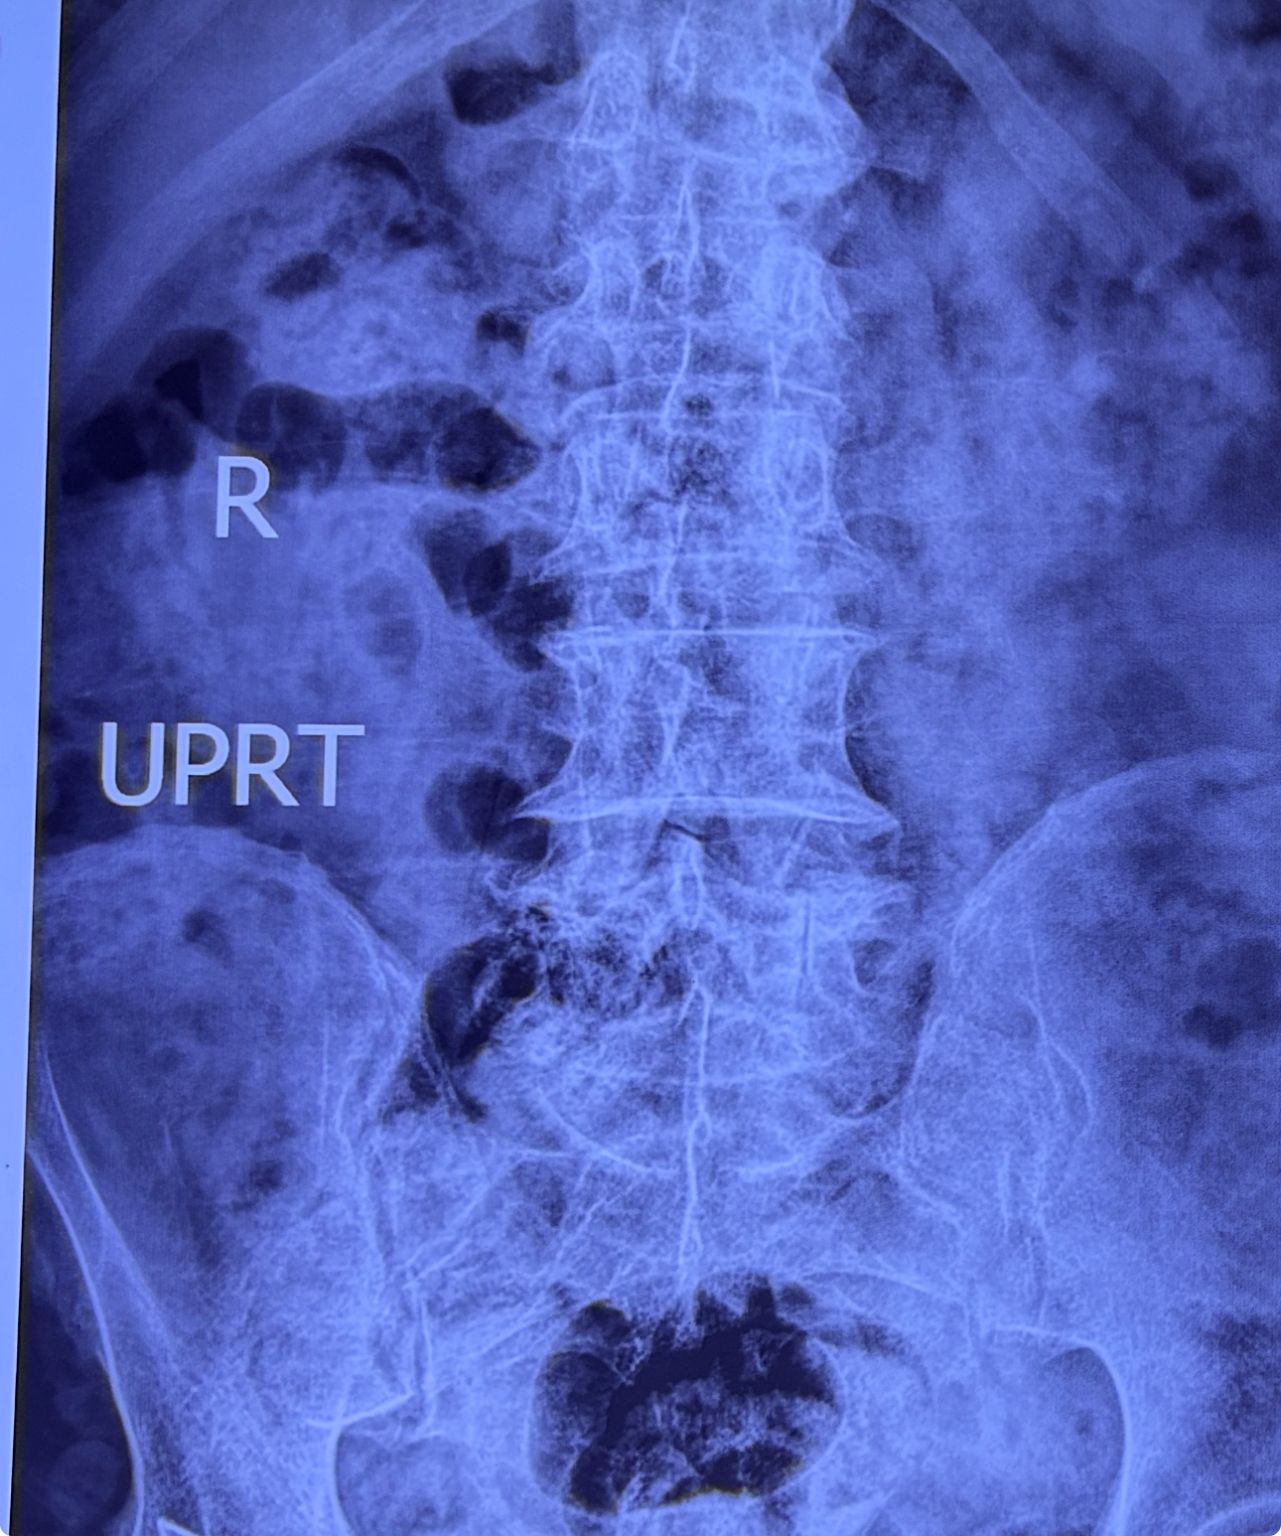

This time presented to my cl with LBP mainly during sleep at night. Just brought me her mri. According to her mri I ordered dynamic L/S X. R.

I didn’t accept her to give treatment. I referred her to her surgeon. What are your findings in her mri and X. Rays?

Is ant listhesis of L4 unstable or stable?

From several compression fractures we see which of is acute/ subacute and which ones are chronic fx?